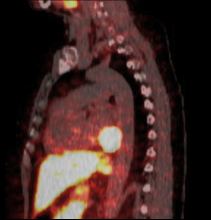

A 59-year-old woman presented with distressing palpitations. Workup revealed a paraganglioma in the posterior left atrioventricular groove. Resection was undertaken en bloc with part of the coronary sinus wall. Reconstruction with autologous pericardium was done. The patient had a smooth recovery.